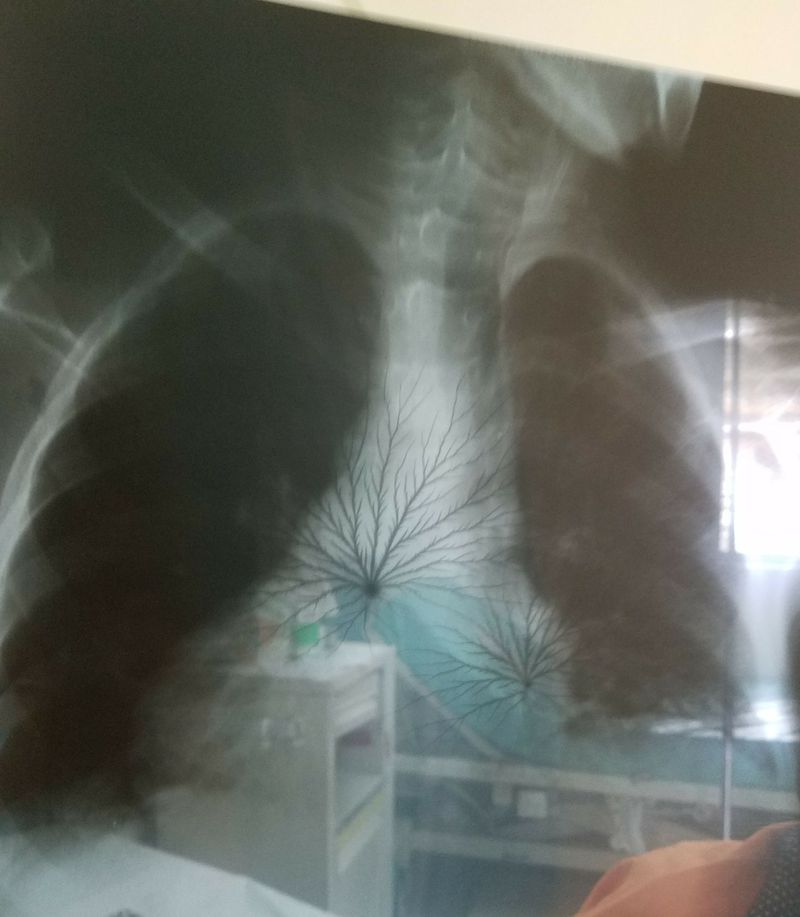

What do you see ?

Xray

Chest

Interpretation

Its look.like malignancy